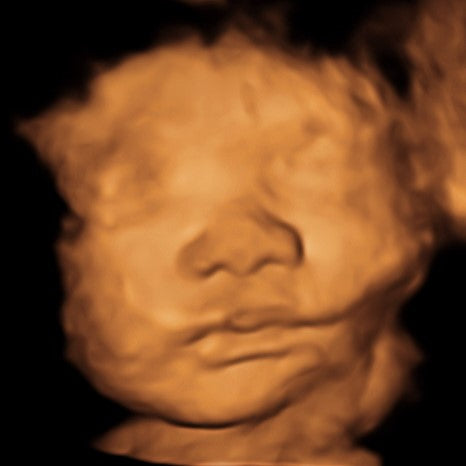

8K

A colorized photo of your baby's 3D Ultrasound